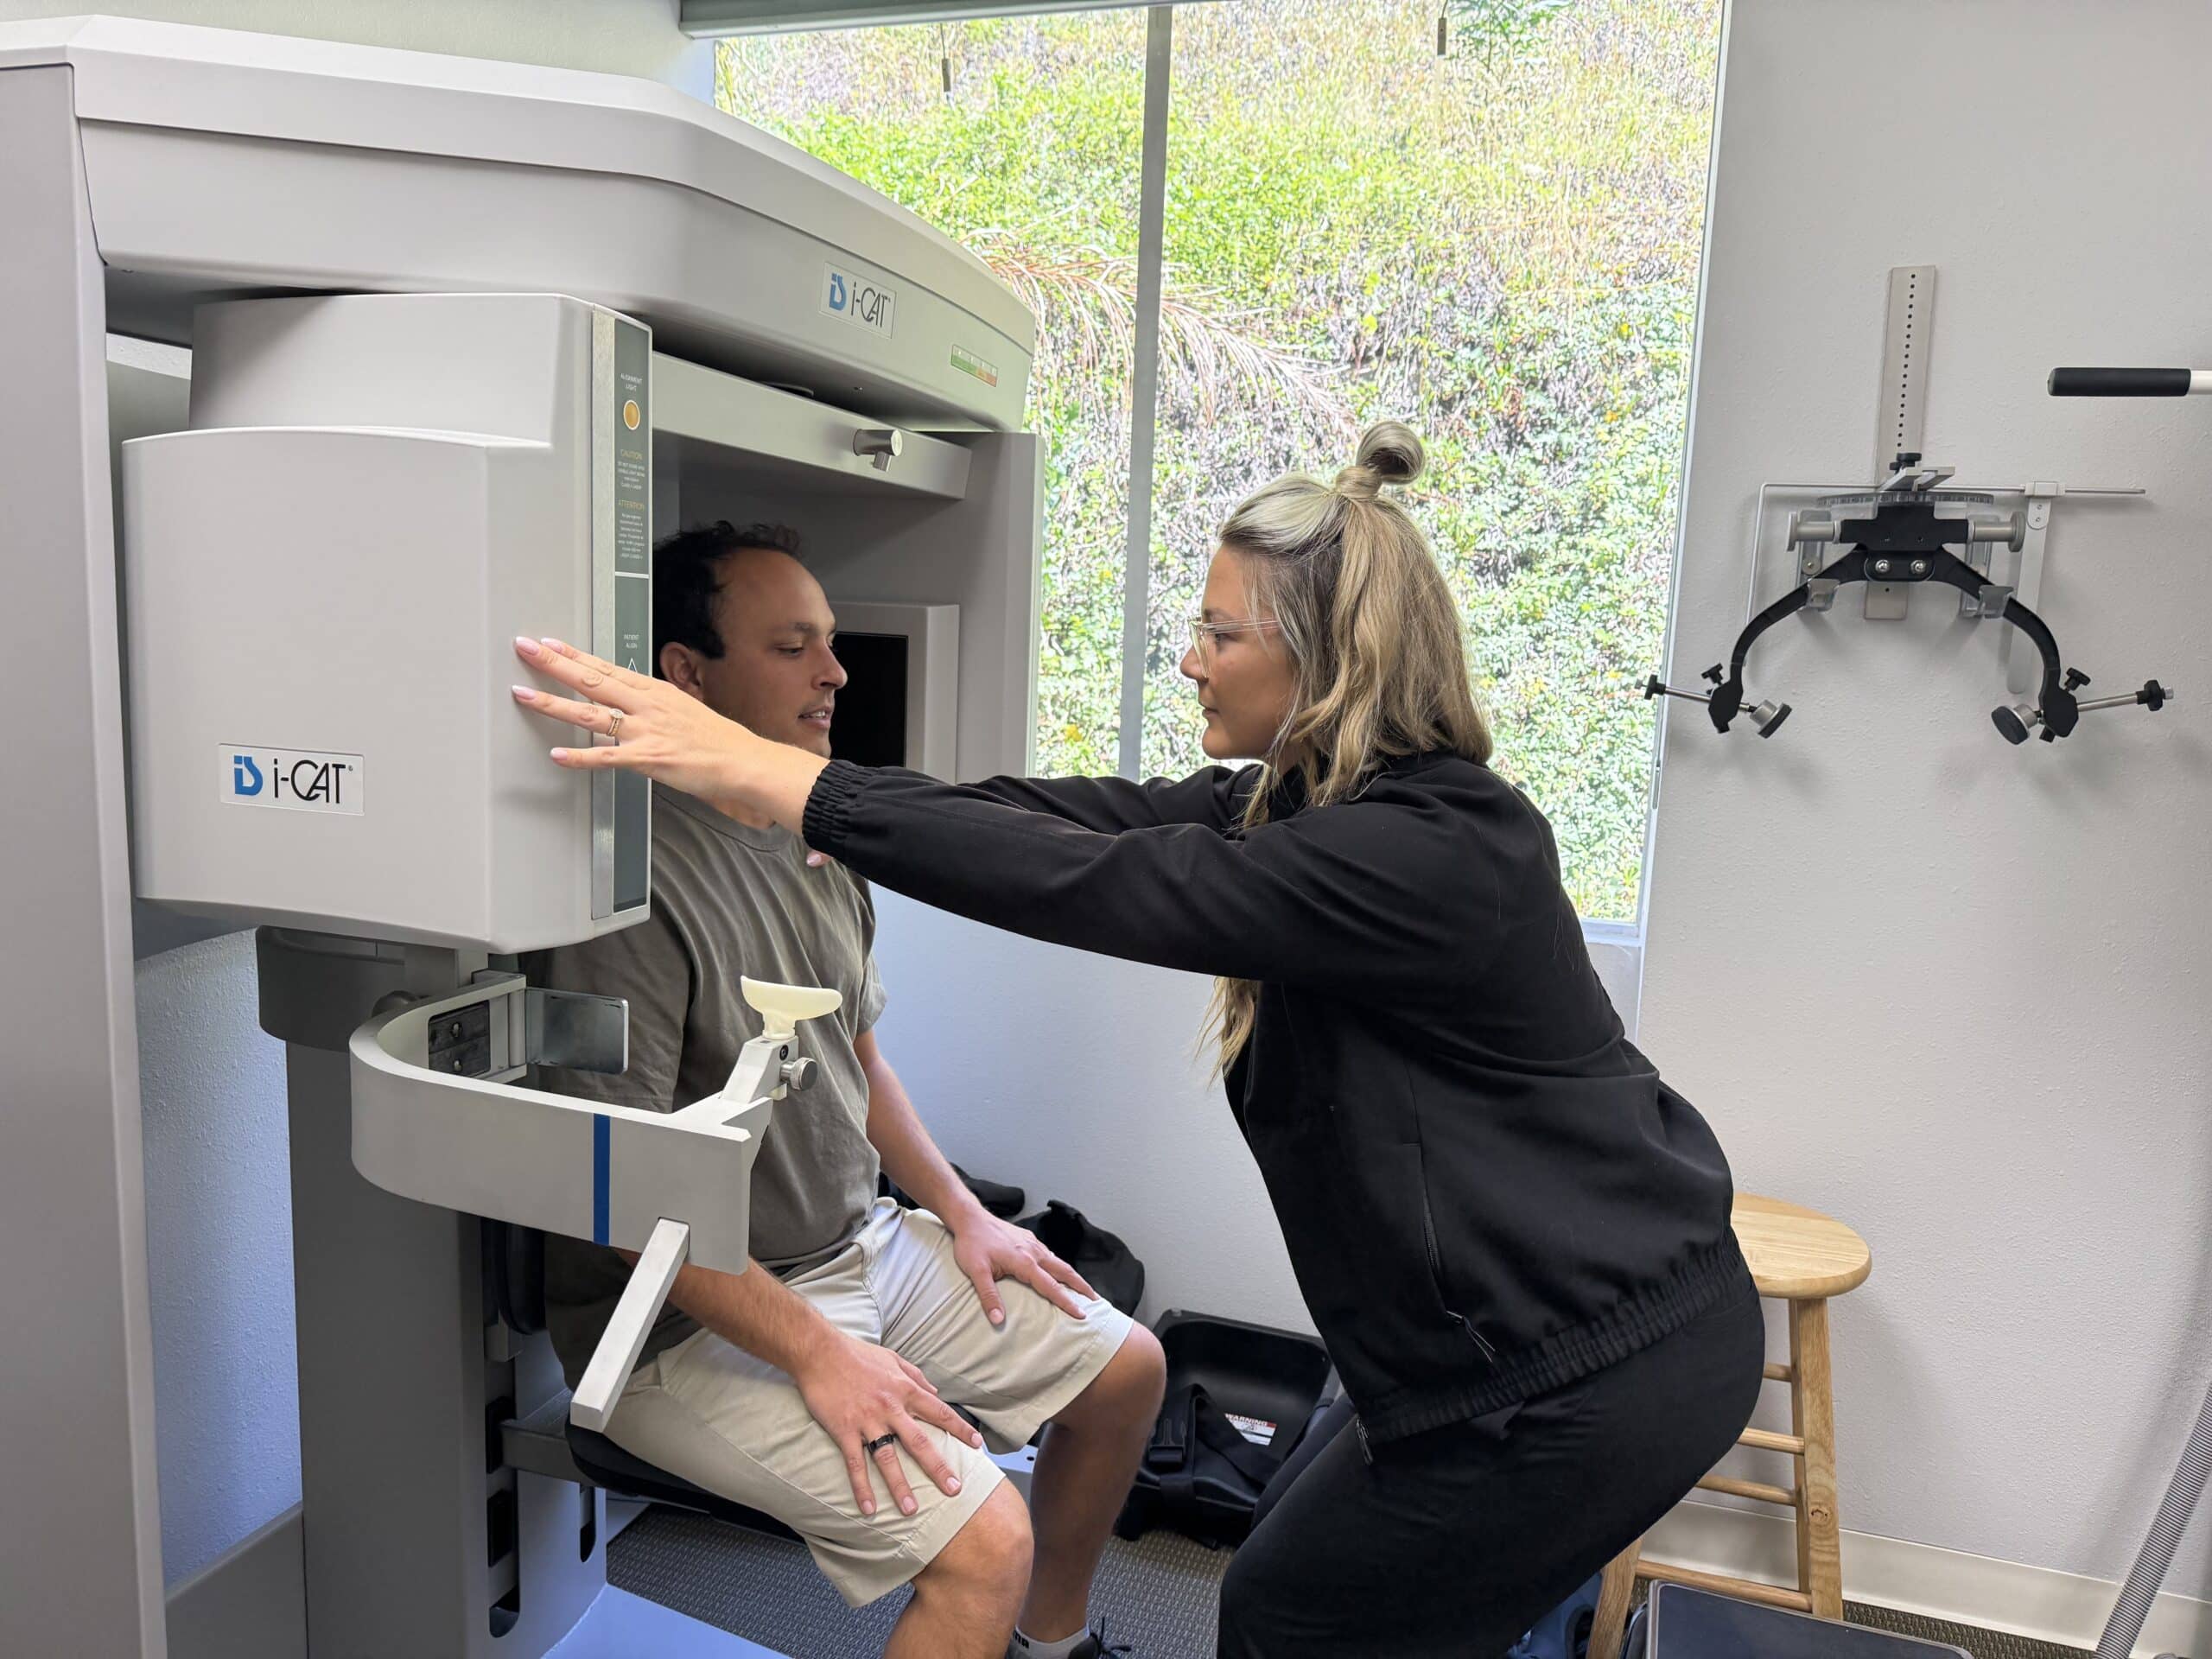

Upper Cervical chiropractors use highly specialized X-rays and adjustments that are specifically tailored to your anatomy. No two people are the same, every individual is unique and therefore has different needs.

Such specialized X-rays allow the doctor to pinpoint which vertebrae are out of alignment and where in space it has moved. No other traditional chiropractor uses this system of analysis except for Upper Cervical doctors.

Cutting Edge Technology

Upper Cervical doctors use a state of the art thermographic scan called the Tytron Scanner to detect imbalance within the nervous system. The Tytron C-5000 (used in our office) can accurately scan the entire spine in less than 15 seconds. A specific heat pattern for the individual patient can be reflective of an upper cervical misalignment.